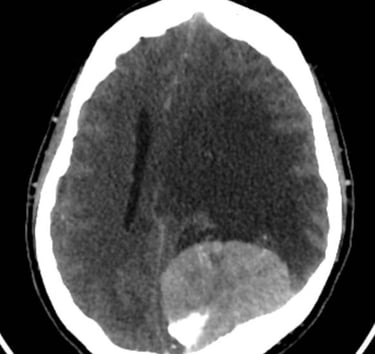

Hemorragias cerebrales

Diagnóstico y manejo quirúrgico de hematomas y hemorragias cerebrales.